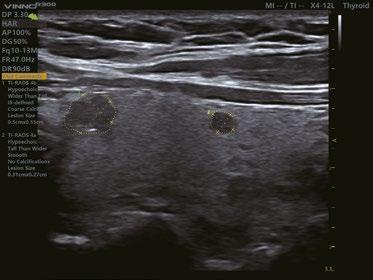

Intelligente Erfassung und Stadieneinteilung von Schilddrüsenerkrankungen

Schilddrüsenknoten werden in Echtzeit oder auf gespeicherten Bildern erkannt, zusammen mit dem T-RADS-Kategorisierungs- und Berichtstool, wodurch die klinische Routine der Schilddrüsenultraschalluntersuchung genauer und aussagekräftiger wird.